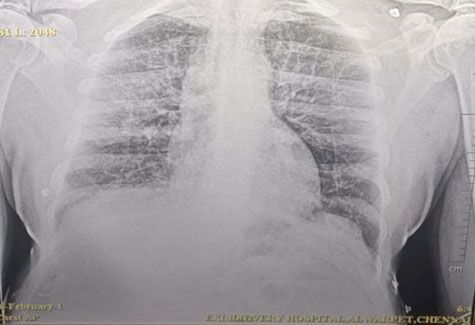

Chest X-ray: Pulmonary Edema